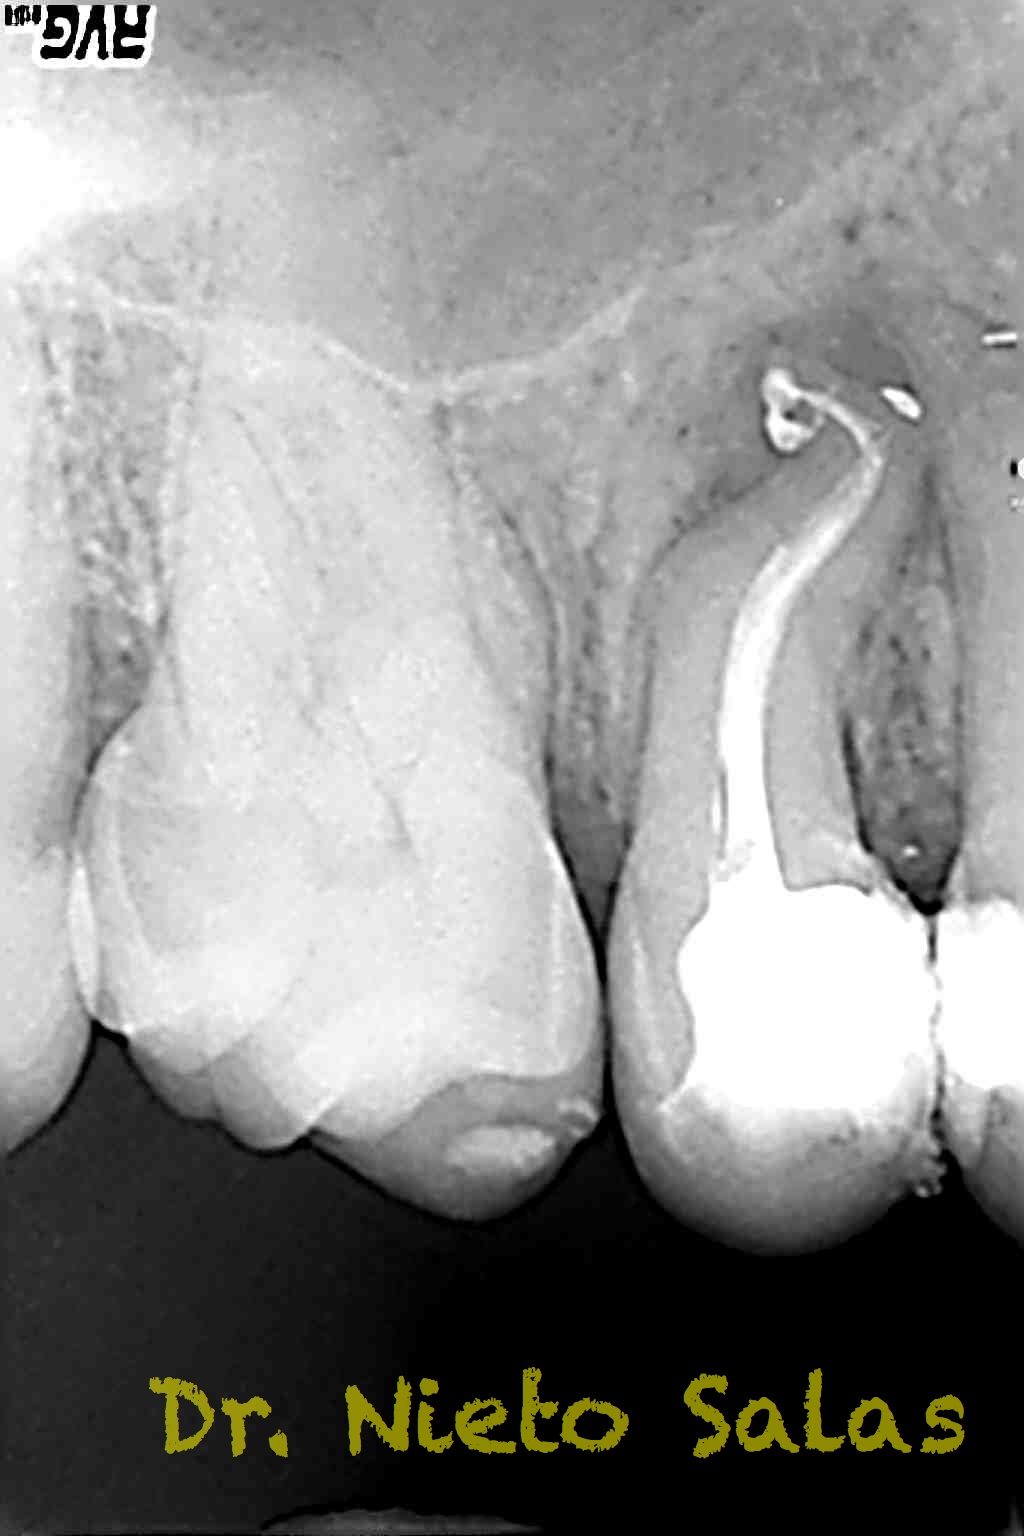

Y  de forma muy similar en el caso B; en este caso el paciente vino a la revisión a los 9 meses evidenciado el éxito en el tratamiento:

Con respecto a lo puramente endodóntico, la verdad que fueron unos casos de verdadero estrés para no perder la permeabilidad ni la long de trabajo, con técnica corona-apice y con un diametro apical de 20, instrumentado solo la parte apical con limas de Mtwo , la parte coronal me ayudé de ultrasonidos. No sé, que más contarte con respecto a la conformación de los conductos.

La verdad, no me planteé la posibilidad de la obturación con Thermafil, se trataba de un caso con un sistema de conductos con un itsmo coronal, y pienso que la obturación con sistema de ola continua me garantizaba un mejor sellado.